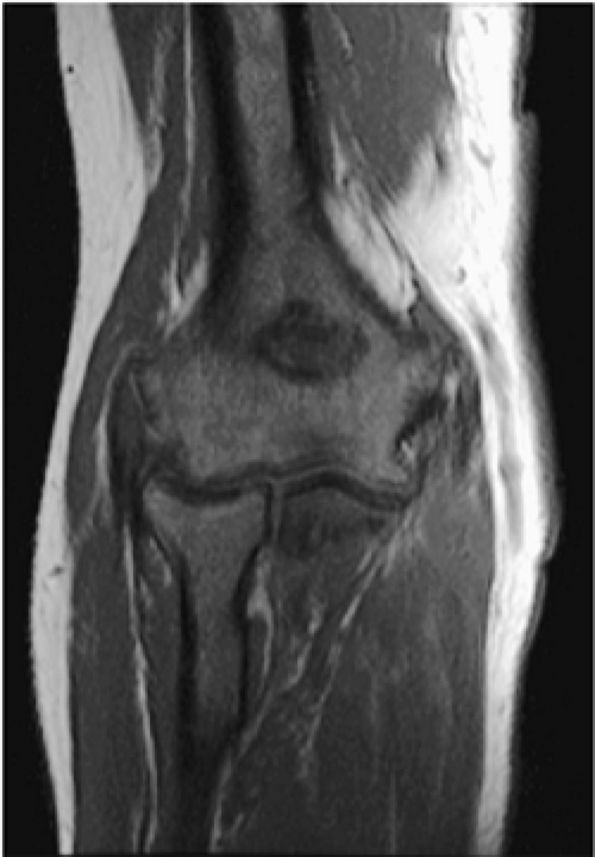

FIGURE 13.14 ● Low-signal-intensity leukemic infiltrates extending into the epiphysis are seen on this T1-weighted coronal image of the elbow. Extension of marrow inhomogeneity crossing the physis is an abnormal finding that may be seen in acute myelogenous leukemia.